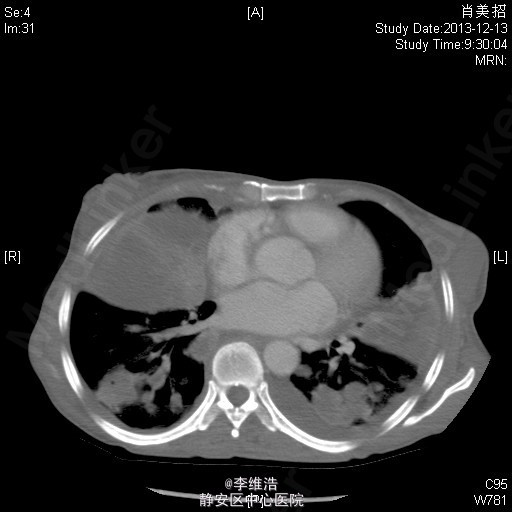

患者,女,53岁。因“咳嗽、咳痰、发热2月余”入院。 2月余前出现右耳听力下降,流脓,后出现咳嗽、咳白痰和脓性痰,伴盗汗、发热、咯血。1月前出现腹胀明显,纳差,双下肢水肿。曾予各种抗菌素治疗,无明显效果。

T38.8 ℃,P118 次/分,R20次/分,BP132 /71 mmHg。精神差,慢性病容,面色苍白,双侧颈部及锁骨上可触及数个黄豆小大淋巴结,无压痛,两肺呼吸音粗,可闻及少量湿性啰音,双下肺呼吸音消失。心界不大,心率118次/分,律齐。腹膨隆,可见胃型,上腹硬,有压痛,肝脾肋下未及,肝肾区无叩击痛,双下肢凹陷性水肿。 胸部CT:两肺多发占位,纵膈淋巴结肿大,双侧少量胸腔积液。 左侧颈部淋巴结穿刺:淋巴结反应性增生。 经皮肺穿刺:肉芽肿性炎伴微脓肿形成,并片状坏死。